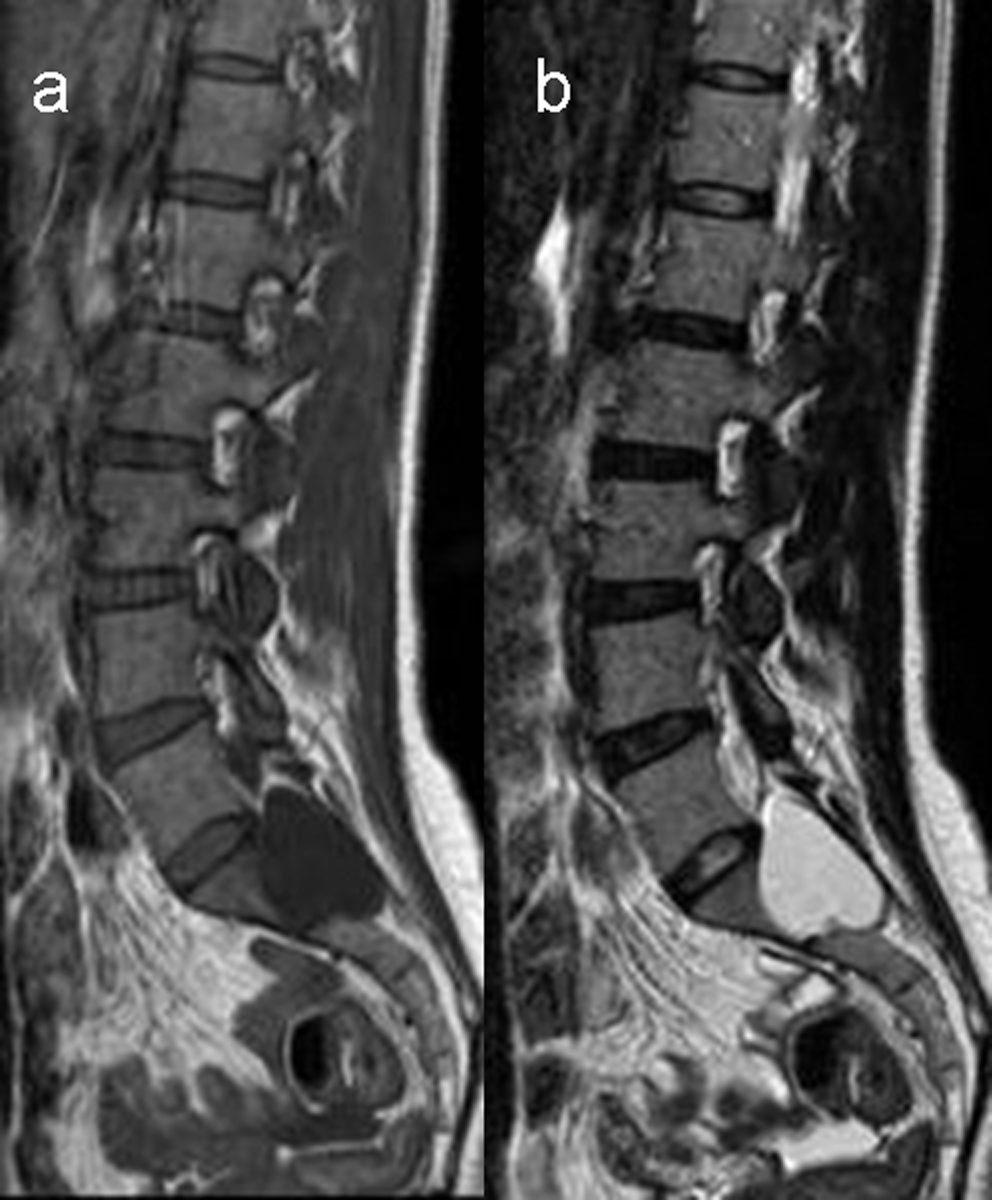

Results: All cystic lesions showed hypointense signal intensity on T1WI and hyperintense signal intensity on T2WI, but the nerve root showed iso-intensity on T1WI and low signal intensity on T2WI. They were linear in shape on sagittal view, and hypo intense dotted spots within the cysts on traverse view. Surrounding structures of the larger cysts were compressed and had bone erosions in some cases; the spinal canal and the intervertebral foramen on the affected side were enlarged. The lesions/cyst wall showed no enhancement after gadolinium administration.